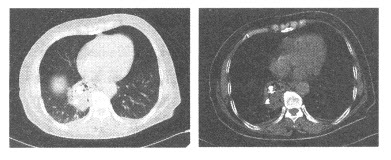

患者,女,50岁。因头晕半年来院检查,影像检查如下图。

(多选题)关于该病例的影像学描述,正确的是()

A:病灶位于左侧颞枕部

B:呈TWI稍低信号,TWI稍高信号,增强扫描明显强化

C:病灶周围可见环形脑脊液信号影

D:病灶宽基底与脑膜相连

E:病灶为脑内肿瘤